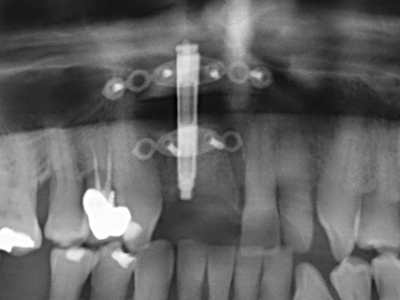

Piezo surgery has additional advantages when harvesting bone blocks. In addition to the high precision with osteotomy described above, the use of the thin saw tips specifically minimizes loss of material. Greater loss of material during harvesting can be expected with the thicker instrument tips, particularly when using Lindemann drills (Lakshmiganthan, Gokulanathan et al. 2012). The basal separation, which is necessary particularly for retromolar block transplants, is simplified by specially designed rectangular saws, with the result that piezo surgery is viewed as a precise, simple and safe procedure for harvesting retromolar bone blocks (Happe 2007) (Fig. 1-12).